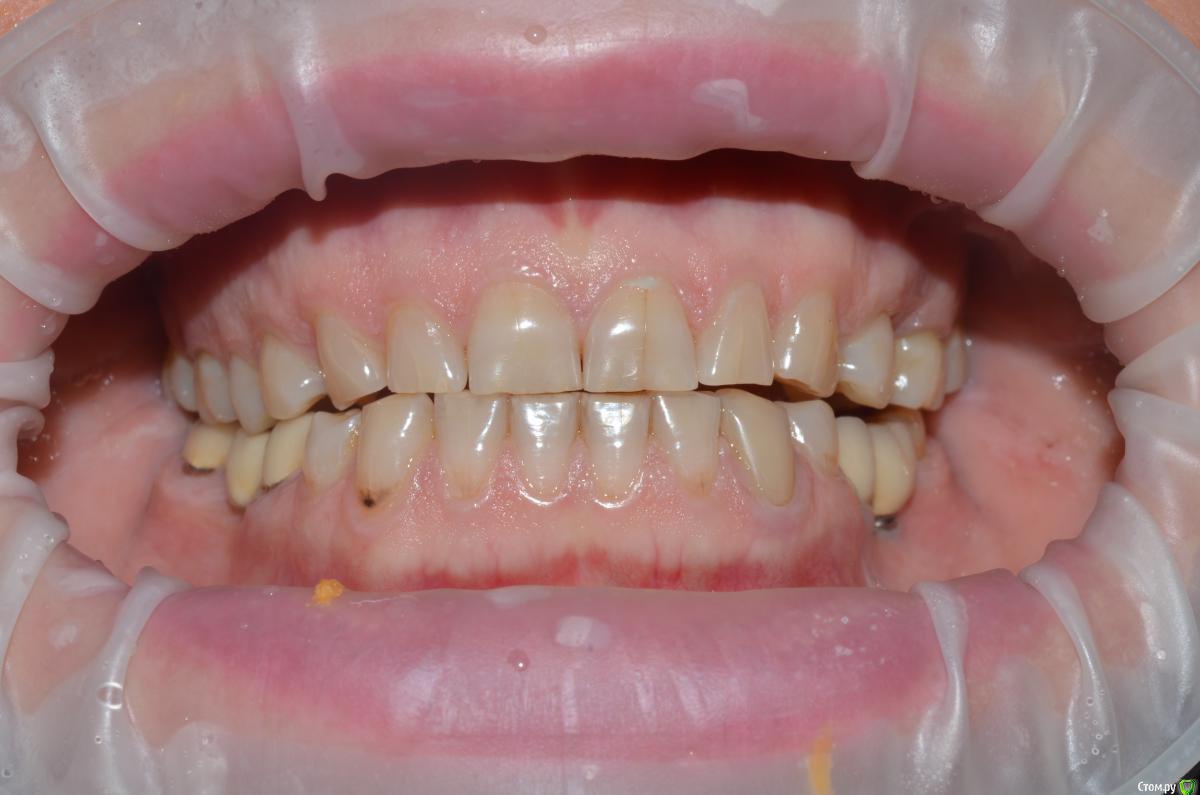

NazranDantist Опубликовано 4 сентября, 2015 Автор Поделиться Опубликовано 4 сентября, 2015 Продолжение кейса. Работа еще не закончена, зуб 25, 35, 36 - аббатменты на подходе, поэтому решили сделать после отпуска пациентки. Фото протокол не соблюдал, курс рубля прыгал, торопился в обменник . Вся работа - имакс на Цереке с редуцированием, фиксация - фронт на чойс, боковые - У-200. Ссылка на комментарий

Freelancer1981 Опубликовано 4 сентября, 2015 Поделиться Опубликовано 4 сентября, 2015 Как цс определяли?Я бы верхние режущий край у верхних зубов(отпрепарированных)загладил,а то разительный контраст с нижними..Фото бы день денька через 3-4.. Ссылка на комментарий

CHEREDNICHENCO Опубликовано 12 сентября, 2015 Поделиться Опубликовано 12 сентября, 2015 Режет глаз смещение цл, оптг необходимо определенно, хотя бы для оценки состояния тттз и периапикальных тканей в 4 секторе.... Индикатор кариеса используете в работе???.... А зачем в 3 секторе оставили временную конструкцию?! Или это постоянная???..... В десятых- эстетически не вяжется соотношение нижних к верхним... PS: В связи с определенным географическим положением, КНДР находиться в 1 км. 44 м. от места моей работы! и хочу сообщить Вам,- уровень их работ растет от из года, в год! Ссылка на комментарий